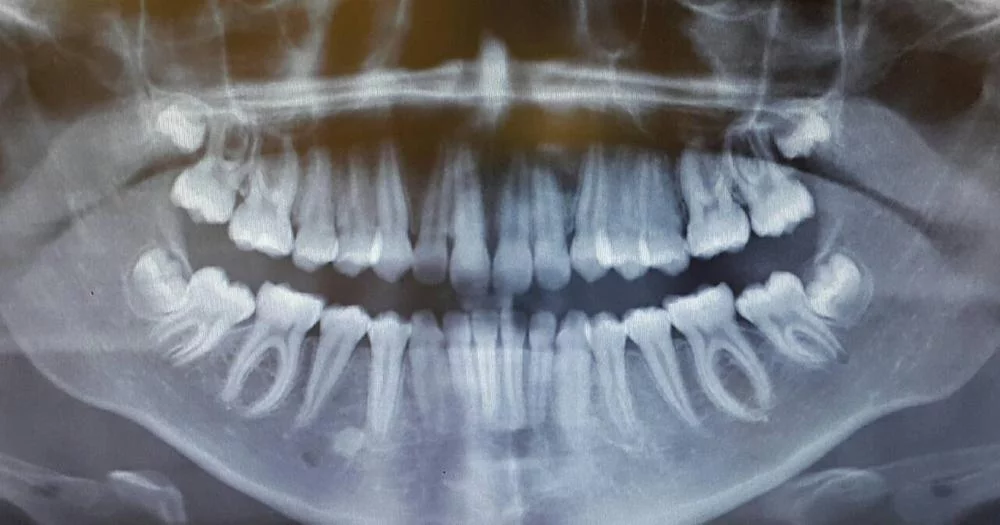

Сделали панораму и КТ, всё

. Будем очень благодарны за советы. Действительно ли всё так плохо, что нужно только все рвать? И какие могут быть варианты протезирования?

Все верхние можно спасти на более-менее длительный срок. Внизу убирать всё и конструкция на имплантах. Наверху в боковых отделах по 2 импланта. Два условия: идеальная гигиена и контролировать уровень сахара.

От реакции на пародонтологическое лечение, индивидуальной гигиены и уровня сахара и будет зависеть дальнейшая тактика.